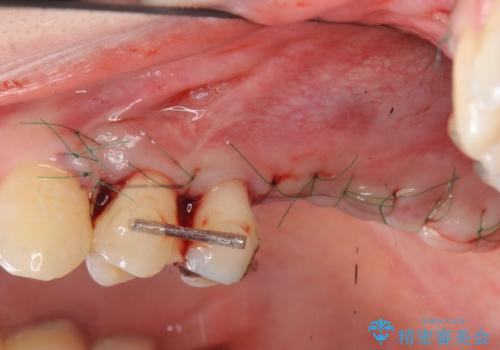

インプラントの仕上がりを見越して、ただ埋入するだけではなく長期的な予後を見込むには清掃のしやすい環境を整備することが大切です。

今回は大きく吸収してしまった歯槽骨をしっかりと造成することで、歯間ブラシを行いやすいインプラント周囲環境を整備することができました。